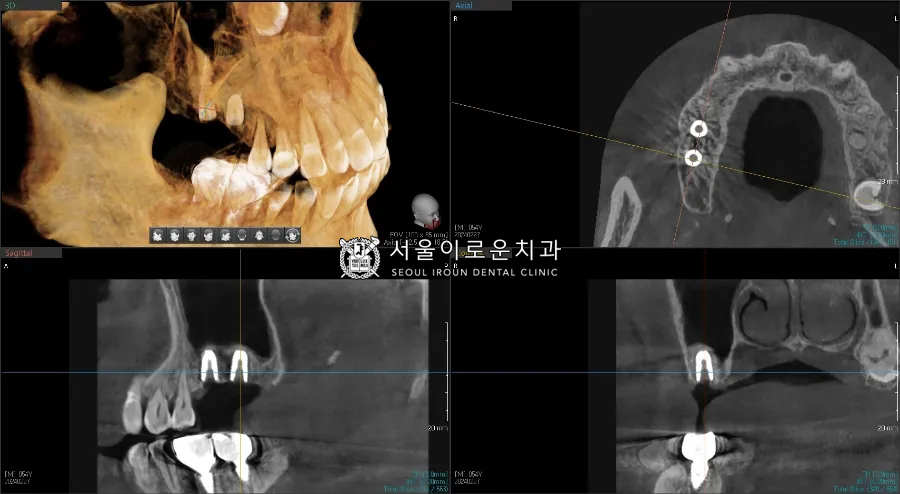

임플란트 식립 전

임플란트 식립 후

바로 다음 치료계획인

오른쪽 위 임플란트 (#16,17)

치료에 들어갔는데요~!

앞서 말씀드린 고난도 임플란트

‘상악동 거상술’을 진행하였습니다!

환.자분의 경우,

발치된지 오래되고

심한 치주염으로 잇몸뼈가

다수 부족하였으나

남아있는 뼈의 높이가 3mm 이상으로

‘치조정 접근법’으로

상악동 거상술을 통해

뼈이식 후 임플란트 동시 식립을

진행하였습니다!